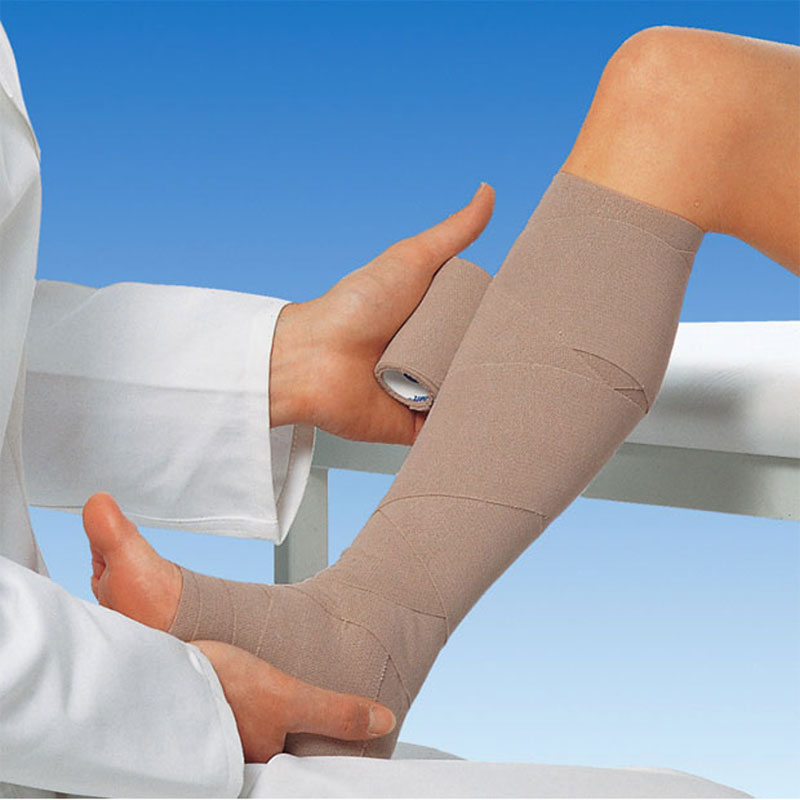

Препарат вызывает контролируемое «склеивание» стенок сосуда, который затем рассасывается. Метод эффективен для устранения невидимых глазу, но патологически измененных подкожных и перфорантных вен. Реабилитационный период минимален.